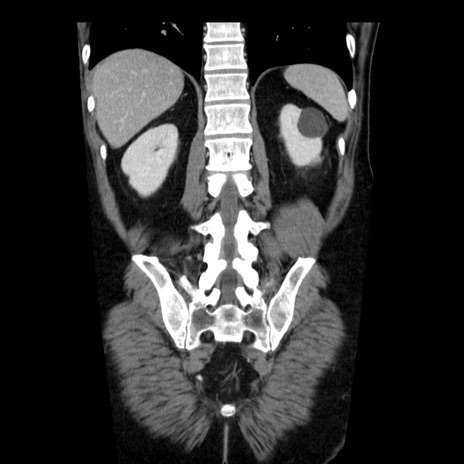

横断像